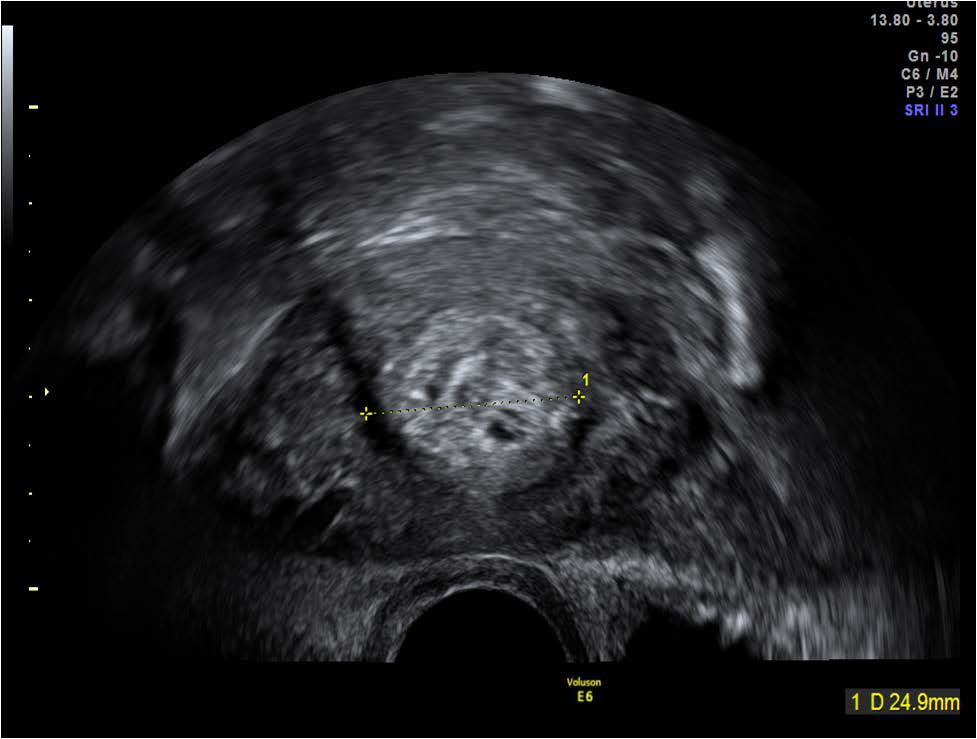

Figure 8: Echogenic mass within the lower uterine segment in the same patient (Figure 7) as seen in the transverse plane on transvaginal scan.

figure 8